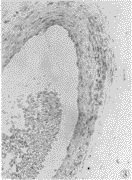

2.1.1 胎盘 胎盘组织内iNOS免疫组化染色显示,正常妊娠组大部分胎盘绒毛合体滋养层细胞不着色,或仅有浅淡着色,残留的细胞滋养层细胞有着色;妊高征者的绒毛合体滋养层细胞较多呈棕黄着色。正常及妊高征胎盘绒毛间质内可见散在的深棕黄色着色的Hofbauer细胞(图1、2)。正常妊娠组胎盘的绒毛干大血管及绒毛小血管平滑肌细胞多着色,内皮细胞扁平,着色少;而妊高征组胎盘的一些绒毛干大血管及绒毛小血管平滑肌细胞着色明显减弱或无,内皮细胞着色增强(图3、4)。

图1 免疫组化:正常妊娠胎盘,绒毛合体滋养层细胞iNOS 染色几乎 无着色。ABC 法 ×100

Figure 1 Immunohistochemistry: Normotensive placenta, the iNOS staining is almost no staining in syncytiotrophoblast . ABC ×100

图2 免疫组化:妊高征胎盘,绒毛合体滋养层细胞iNOS染色呈棕黄色颗粒。ABC 法 ×100

Figure 2 Immunohistochemistry: Preeclampsia placenta, the iNOS staining is stronger in syncytiotrophoblast. ABC ×100